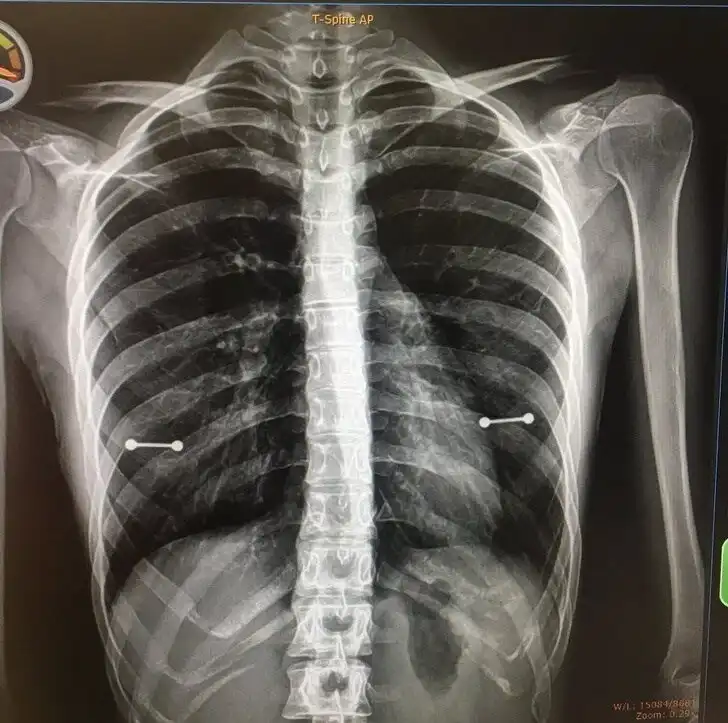

Тот случай, когда рентген выдал маме, что у ребенка есть пирсинг в некоторых очень интересных местах